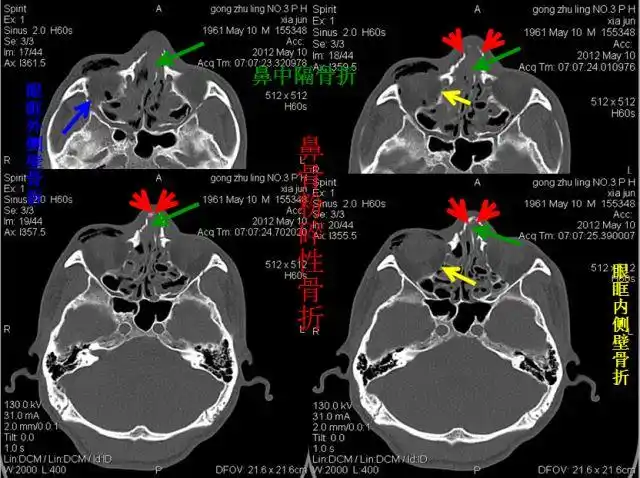

右下:上颌骨额突骨折左下:上颌窦前壁骨折左上:颚骨骨折下颌骨双侧